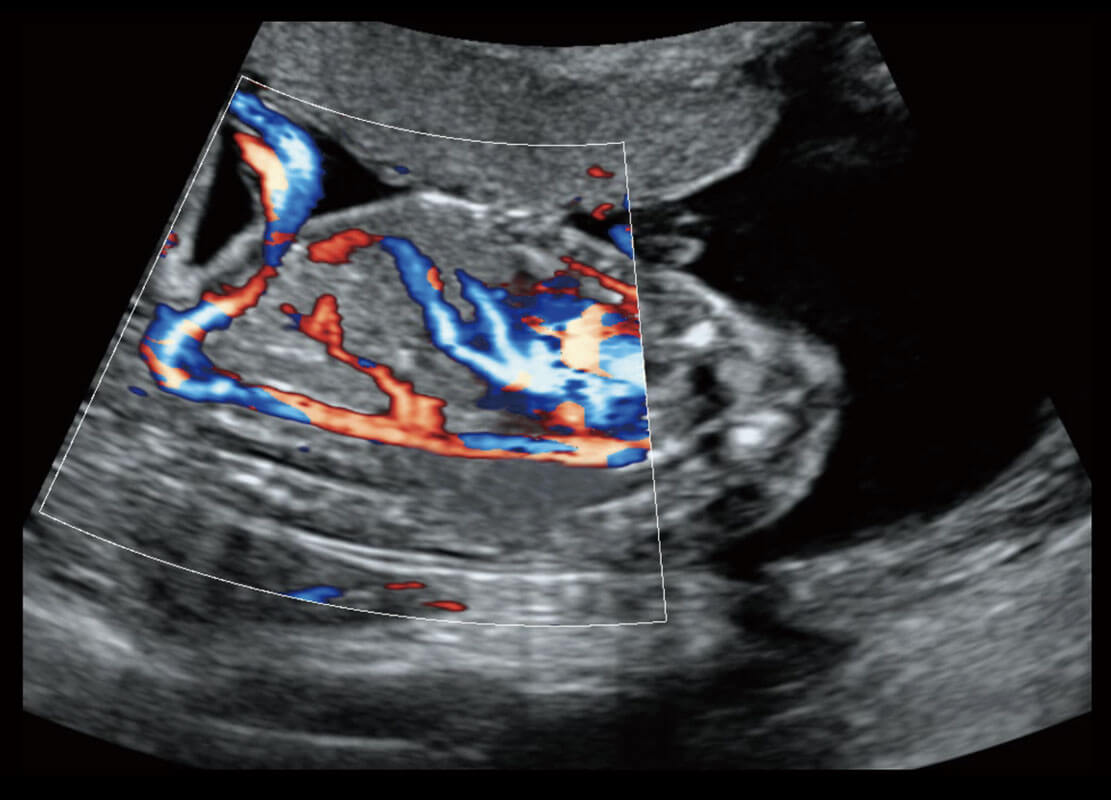

早孕筛查

P60在胎儿早孕期超声筛查中为您带来优异的图像质量。

• 胎儿体循环